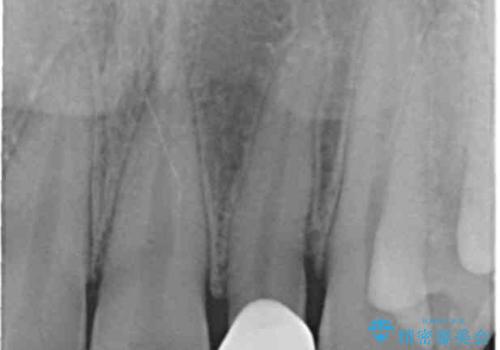

- 左上の前歯の変色が気になるとのことで来院されました。

もともと小さい歯(矮小歯)に樹脂が盛り足されている状態でした。

- 左上2:仮歯+ジルコニアクラウン/11,000円+110,000円費用は治療当時の料金となります

セラミックでの治療をすることにより今後の変色を抑えることができます。

色・形ともに改善することができ大変喜んでいただけました。